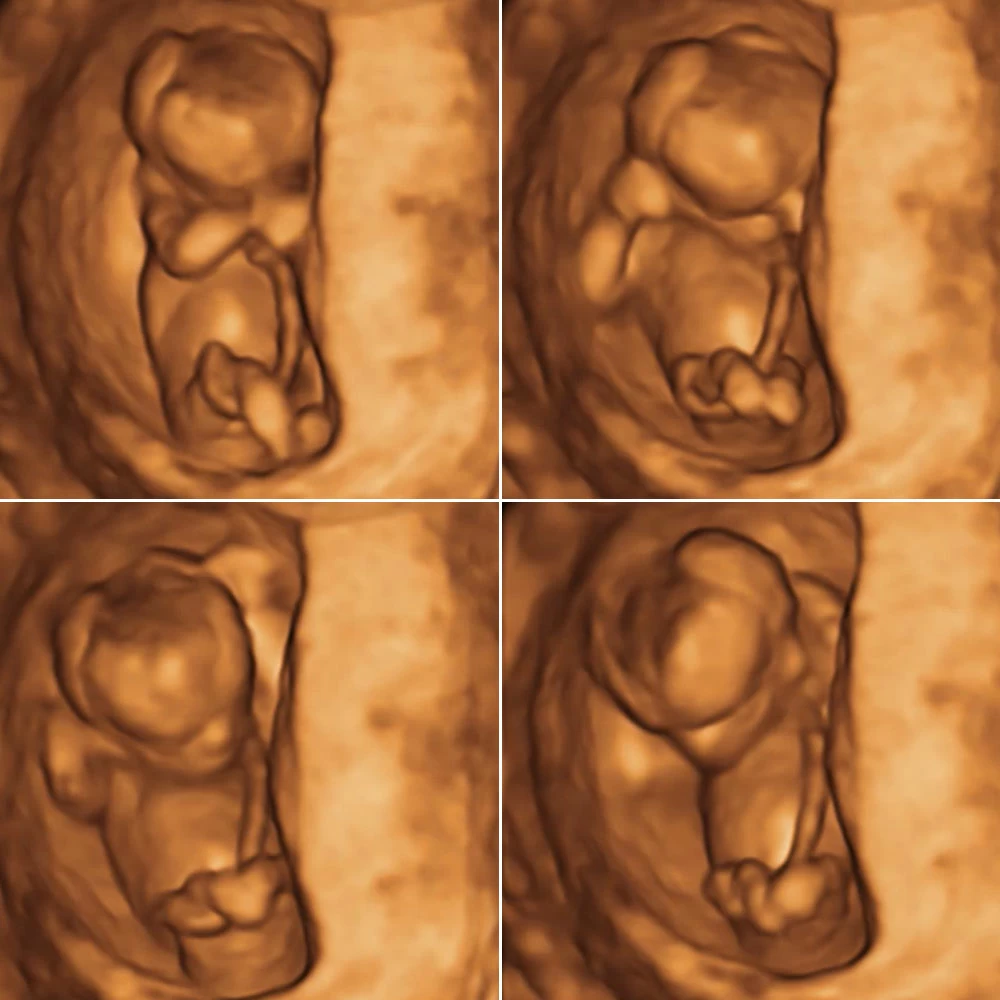

Самая точная УЗ-диагностика с помощью аппаратов премиум-серии